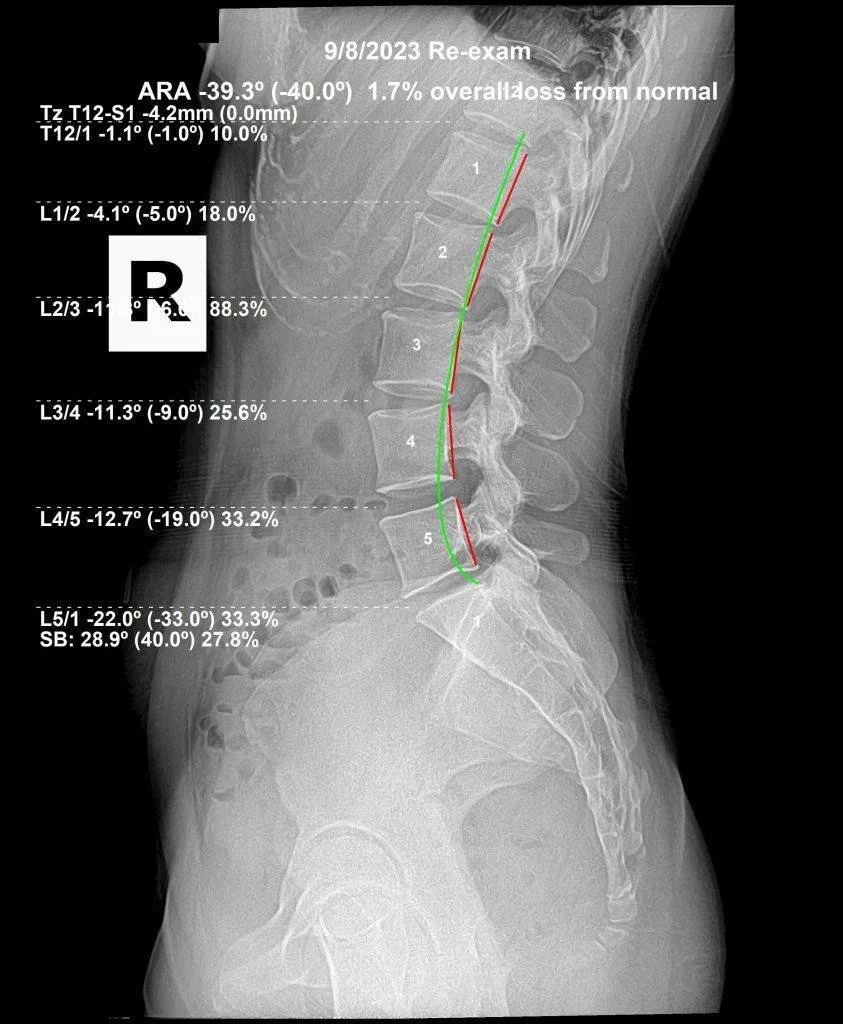

Re-exam lumbar X-ray after subluxation correction — 1.7% loss from normal

Re-exam · 1.7% loss from normal

Actual patient X-rays — lumbar subluxation correction tracked with before and after imaging at Rochet Family Chiropractic.

Subluxation-based correction works differently. The goal is to restore the vertebra to its correct structural position — measured by before and after X-rays — so that the nerve irritation, muscle guarding, and disc stress are removed at their source. When the structure is corrected and maintained, the body no longer has the mechanical reason to produce that recurring pain response.

It depends on how long the subluxation has been present and the degree of structural distortion. Recent subluxations correct faster than patterns that have been present for years. Most patients notice functional improvement within weeks; measurable structural correction — confirmed by progress X-rays — typically develops over months of consistent care. Dr. Rochet will give you a specific timeline based on your initial X-ray findings.